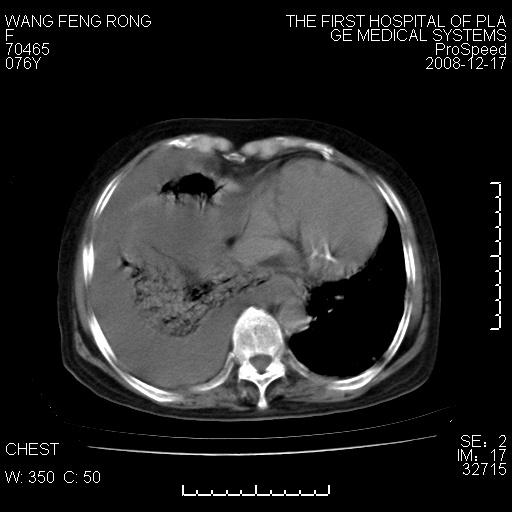

右肺大部实变,其内可见支气管影,但分支减少,宽窄不均,走行僵直,同侧胸腔大量积液;纵隔内见多发淋巴结影,但淋巴结大部有钙化;主动脉壁钙化;临床上病人咳嗽、消瘦。所以我考虑:1、结核(依据:右下肺实变,纵隔内淋巴结符合结核表现,同侧并发胸膜炎表现);2、支气管肺泡癌(依据:实变的肺组织内支气管分支减少,宽窄不均,走行僵直,没有把它放在第一诊断是因为没有看到明显肿大的淋巴结);3、动脉硬化(主动脉壁钙化就支持这个诊断)。

1)考虑两肺炎症感染;不排除肺泡癌可能。2)两肺间质纤维化。3)右侧胸腔积液。

病理结果,肺泡癌